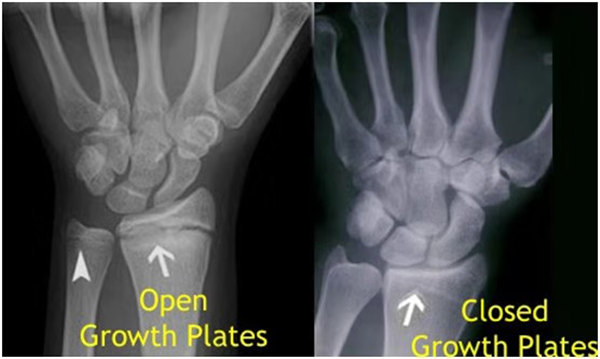

我們都知道,人體的高矮是由骨骼的生長發育決定的,特別是下肢長骨。長骨呈長管狀,在長骨的兩端有一種專管骨骼生長的骺軟骨,它與干骺端之間有一盤狀軟骨結構稱為骺板(線),在幼兒的X光片上表現為一條較寬的透光帶。 (見下圖)

未成年時隨著年齡的增加骺軟骨端不斷骨化,骨骼就不斷增長。當骨骺線完全閉合時骨骼就停止生長,個子也就不再增長了。一般骨骺端完全閉合的年齡是18~20歲左右。

一般來說,女孩的骨齡超過14歲,男孩的骨齡超過16歲,這時其骨骺線已接近閉合,基本沒有長高的機會了。

因此,越早了解骨骺線閉合情況,越早干預,孩子長高的可能性越大。